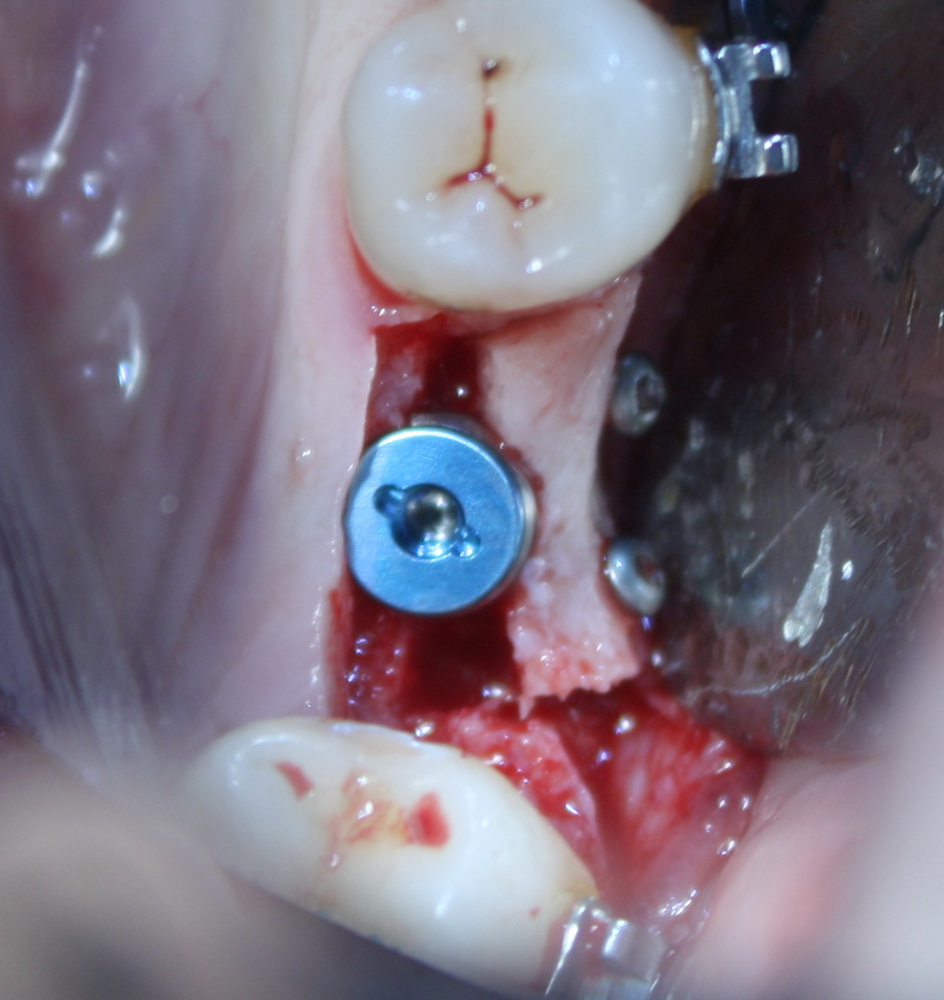

Как, например, на картинке выше — тут и удаление, и остеопластика, и еще два импланта. Вот тут антибактериальная профилактика по-любому нужна.

— если время операции — больше 60 минут. Среднестатистическая операция остеопластики в это время легко укладывается. Например, такая: